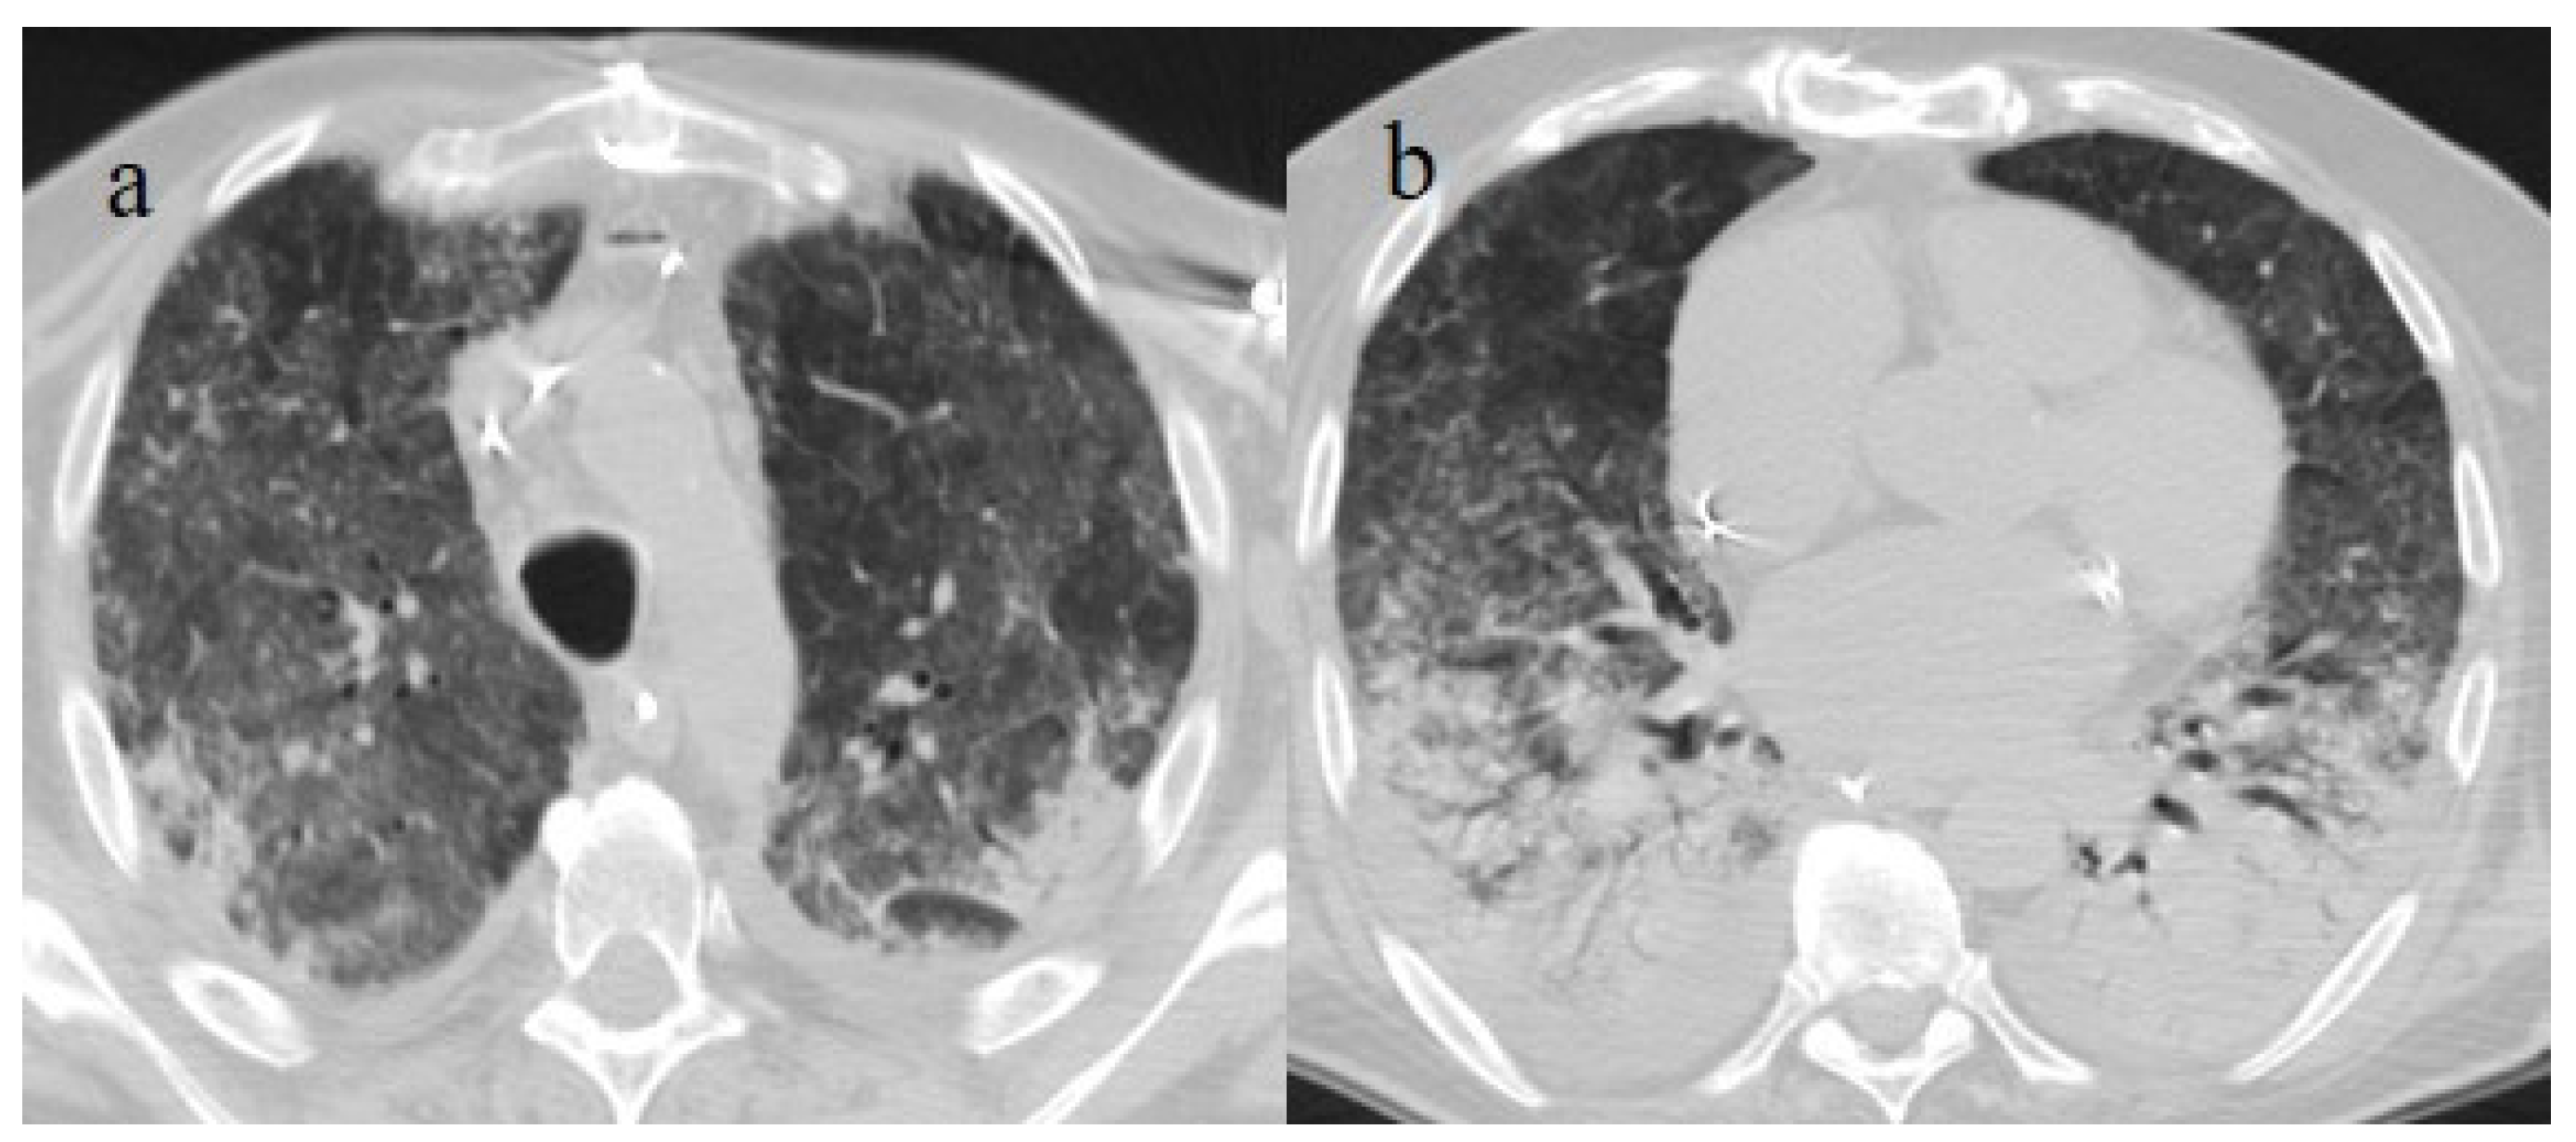

| Typical Appearance | GGOs with a crazy-paving pattern and consolidations in a peripheral and posterior or central-peripheral distribution; multilobar involvement; vascular enlargement, the halo and reversed halo sign; subpleural and parenchymal bands; and architectural distortion. They were predominant since the Delta wave. |

| Indeterminate Appearance | GGOs and consolidations with a unilateral, central, or upper-lobe distribution. |

| Atypical Appearance | Lobar consolidation, lung nodules or masses, miliary patterns, tree-in-bud patterns, cavitation, pleural effusion, central distribution, and lymphadenopathy. Atypical appearances were predominant during the Omicron waves. |

| Typical appearance | From the wild-type to the Delta variant. | Askani et al., 2022 [67] | The Delta variant presented more frequent typical features with more extensive lung involvement than the Omicron variant. The Omicron variant was more frequently associated with the absence of pneumonia. |

| Inui et al., 2021 [68] | Typical findings were characteristic of the wild type to the Delta variant. GGOs with consolidation and repair changes were more frequent in the Delta variant. The Delta variant also showed more rapid pneumonia progression than the wild-type and Alpha variants. | ||

| Ito et al., 2022 [54] | Peripheral GGO distributions were more frequent in the Alpha and Delta variants than the Omicron variant. | ||

| Kirka et al., 2022 [27] | Typical features were found in 40.8% of patients with the wild-type variant and 1.7% of patients with the Omicron variant. | ||

| Lee et al., 2023 [28] | Typical CT patterns were more frequent in the Delta group (76%) than in those with the Omicron variant (42%). | ||

| Yang et al., 2022 [78] | Of patients with the Alpha variant, 86.84% presented typical COVID-19 pneumonia CT features. | ||

| Yoon et al., 2023 [69] | Only 32% of patients with the Omicron variant presented typical findings, compared with 57% of the Delta variant cases. | ||

| Indeterminate appearance | Omicron variant | Ito et al., 2022 [54] | Cluster-like GGOs in the Omicron wave. |

| Atypical appearance | Omicron Variant | Hang et al., 2023 [75] | Patients infected with the Omicron variant presented a significantly higher prevalence of nodules, tree-in-bud patterns, and halo signs than patients with the original strain. |

| Ito et al., 2022 [54] | Prevalence of non-peripheral distribution with random distribution during the Omicron wave. | ||

| Lee et al., 2023 [28] | Peribroncovascular pneumonia with the Omicron variant and lower rates of severe pneumonia than the Delta variant. | ||

| Tsakok et al., 2023 [77] | Patients with an Omicron infection presented a greater frequency of bronchial wall thickening but less severe disease compared with the Delta variant. | ||

| Yang et al., 2022 [78] | Only 1.3% of patients infected with the Omicron variant had foci of pneumonia, and the GGOs were unilateral and centrilobular. | ||

| Yoon et al., 2023 [69] | Peribroncovascular GGOs or centrolobular foci during the Omicron wave with less extensive pneumonia. |